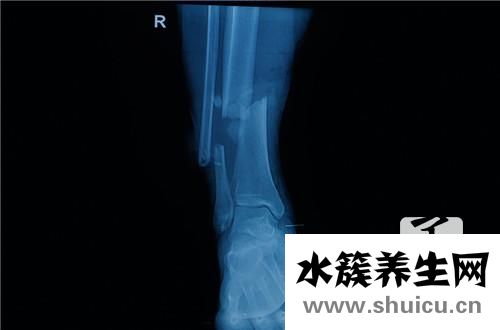

骨癌是一種常見的腫瘤疾病,主要由骨組織中癌細胞的存在引起。 通常,難以確定骨癌的存活時間。 在這里,我們將專門介紹一下骨癌可以存活多長時間。

骨癌能活多久

骨癌能活多久呢?對于這個問題,則是很難回答的。因為患者的生存時間跟患者的病情、體質以及治療和心理都有很大關系的。因此有些骨癌患者可以活十幾年,而有些患者則只能活幾個月。

骨癌晚期能生存多久這主要是與患者的治療方法有關,視不同的治療方法、病理類型、分期、病人狀況,生存率也是不同的,幾個月到數年,甚至十多年都是可能的,要具體分析,沒有一概而論。

一個成功的骨癌手術能大大提升腫瘤患者的生存率甚至達到治好,但這并不是唯一的原因。關于骨癌手術后能活多長,其還受是否是治療最佳機會、手術前手術后患者護理、腫瘤患者心態、腫瘤患者身體性能等等原因的影響。

骨癌腫瘤患者手術后到底能活多長,最重點的取決于以下四個在那方面:

1、只要是惡性腫瘤,術后能活多長重點看是把握住了最佳手術治療機會。但大部分骨癌早期的找到較艱苦,就診時多為中晚期。假如是普查找到的癌腫,往往偏早,對手術后患者的生存率很有幫助。對于骨癌特別危險人群,最好能一年查體1~2次,對骨骼作通常X光片攝影,有助于早點查出骨癌。

2、對與患者來說,能正視疾病,保持一個平和的心態,積極配合手術治療,對延長手術后的生存時間很有幫助。部分腫瘤患者可能要面臨截肢,這無疑是個沉重的打擊,醫護人員和家屬必須說明腫瘤手術的必要性,多和腫瘤患者溝通,使其保持良好的心態積極接受治療。

3、治療方法是否得當,腫瘤手術是否徹底,治療是否及時,在很大程度上影響了骨癌手術的生存時間。根據腫瘤患者癌腫病理病因分期,身體狀態,及時采用最合適的手術治療,鏟除腫瘤,能延長患者術后存活時間。